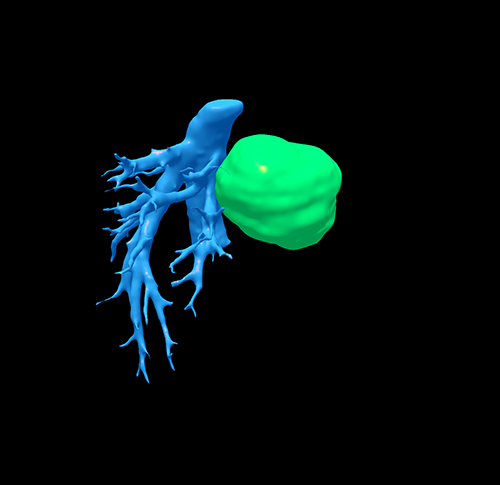

左肝肝癌---扩大左半肝切除+尾状叶切除